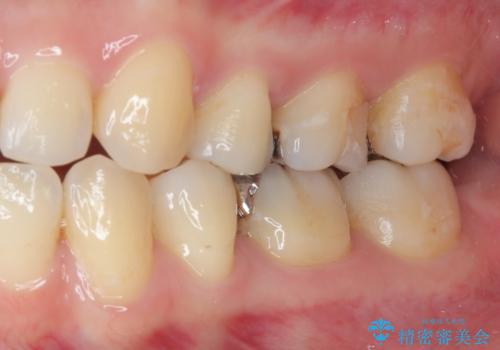

痛みやしみることもなく、適合もよく、機能的に問題もなく、見た目も満足されていました。

今後は他の金属の詰め物(メタルインレー)のところを治療していく予定です。